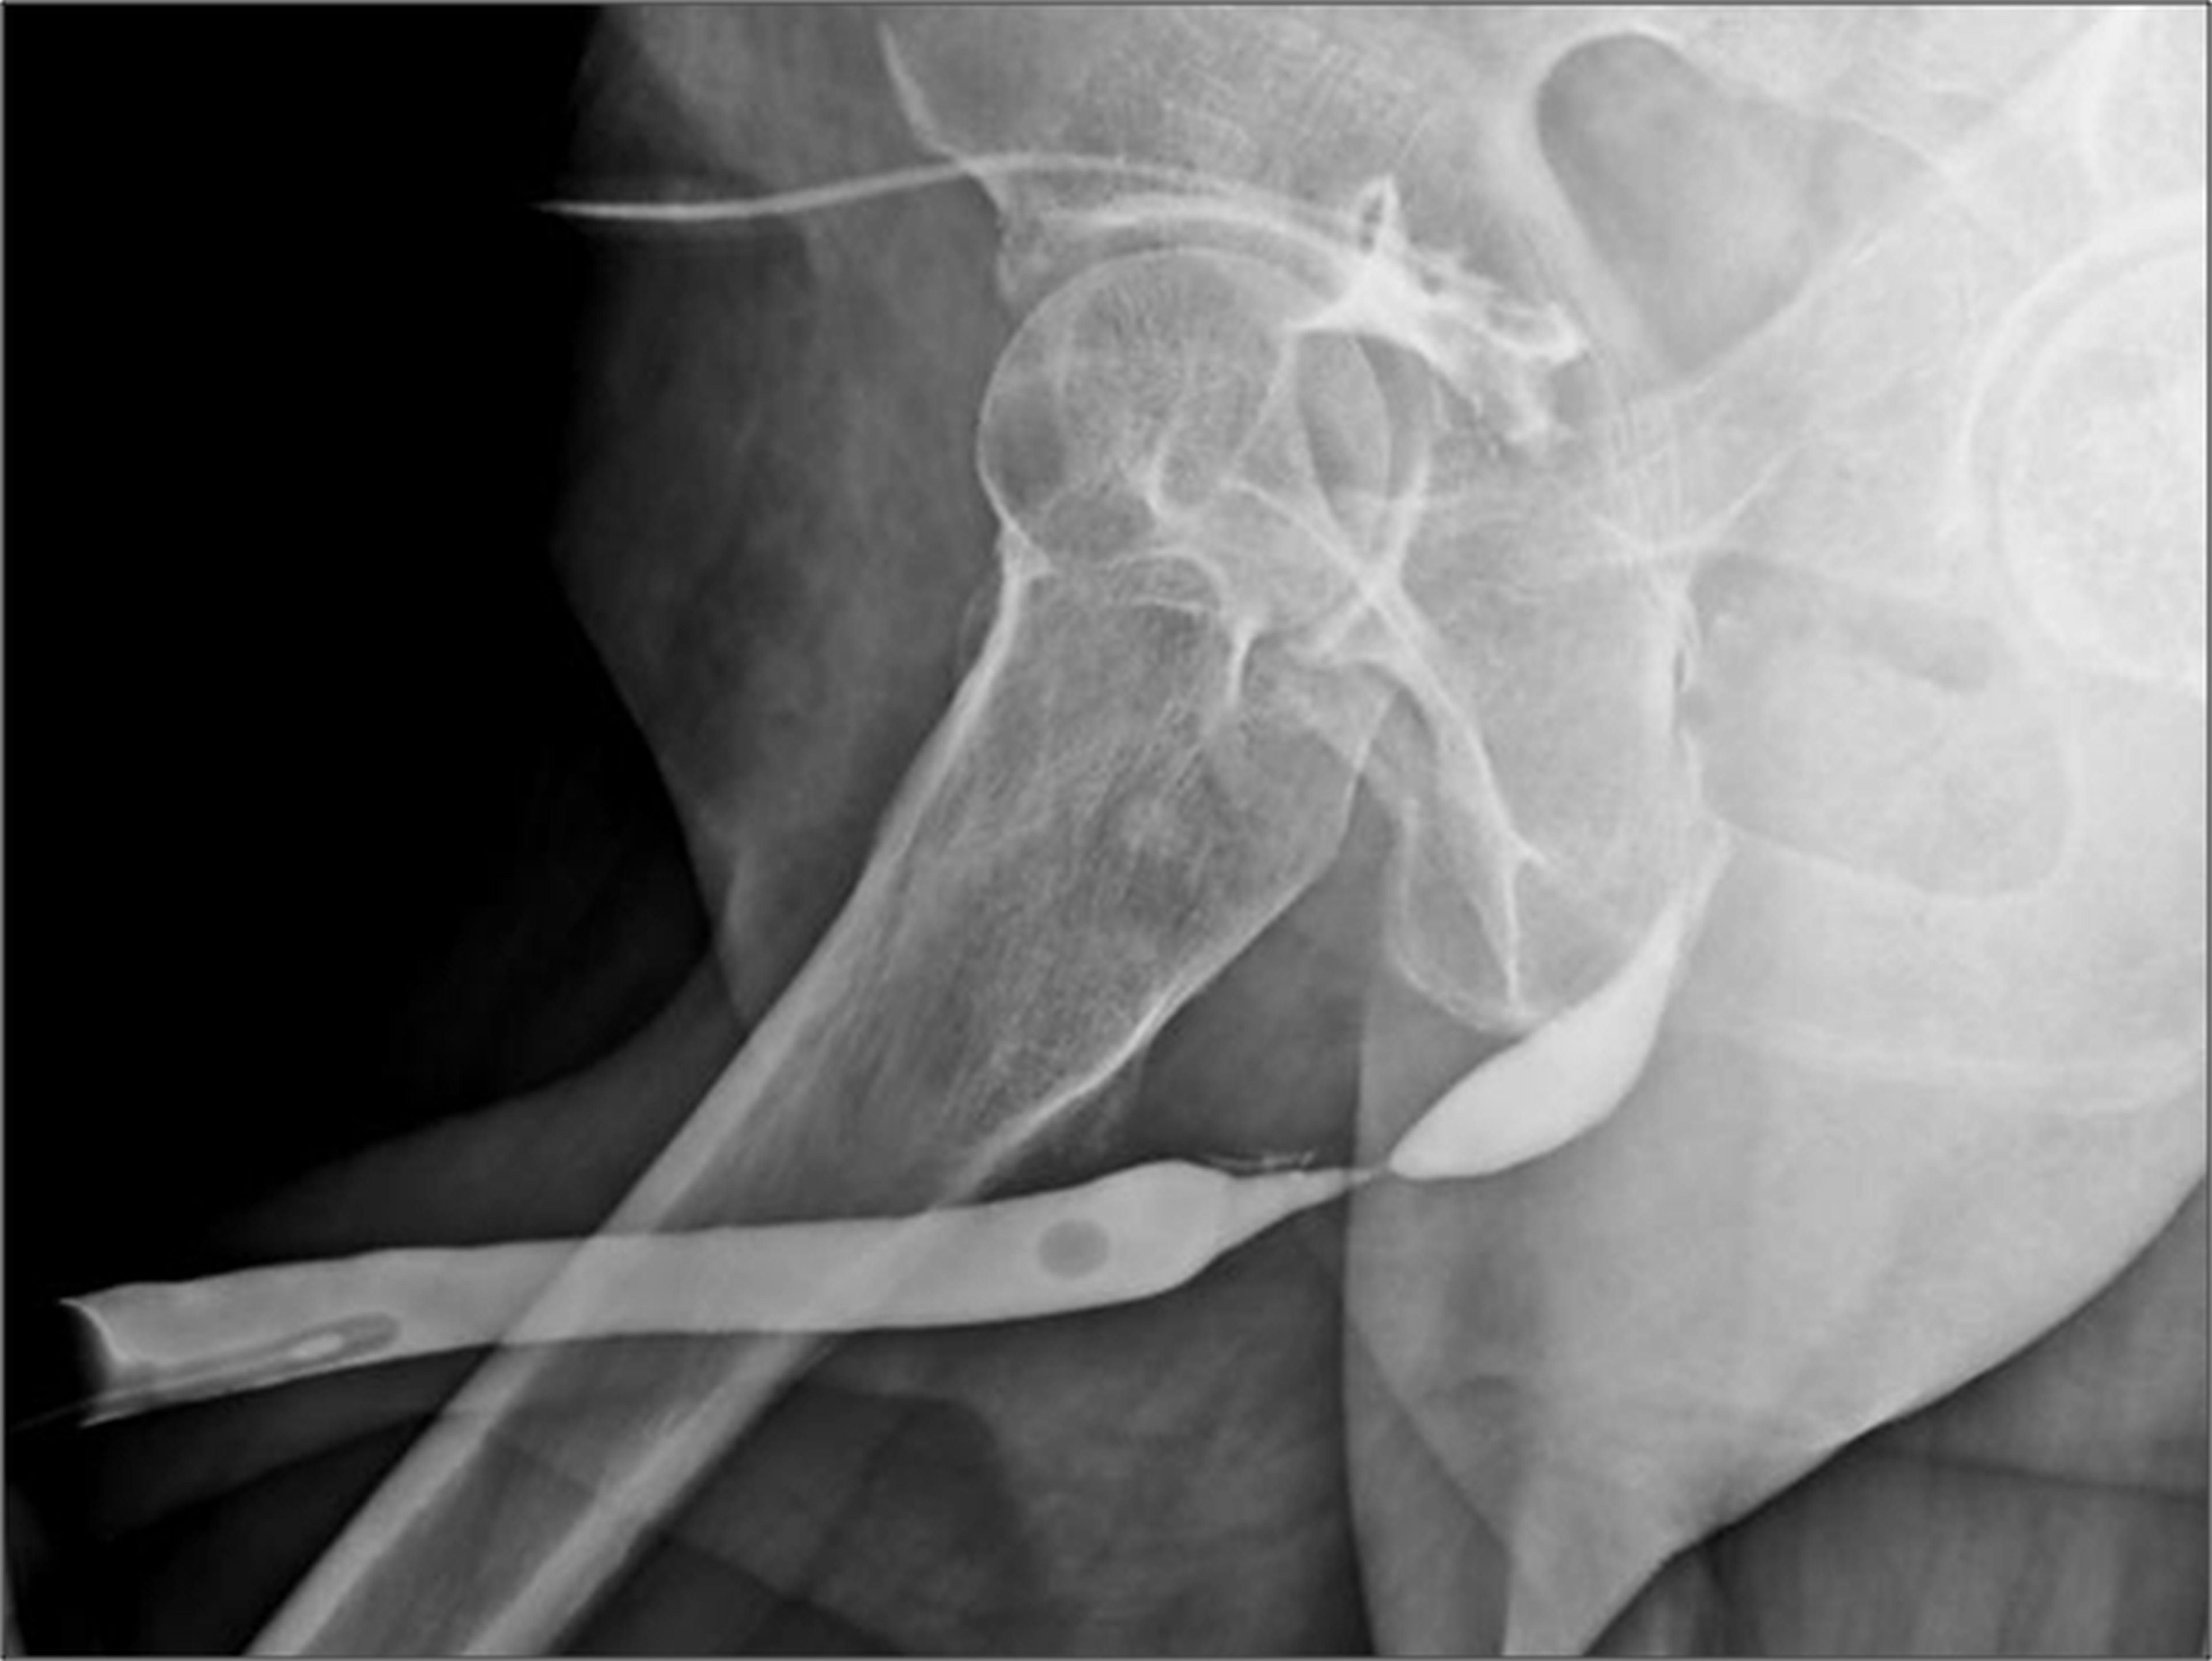

Stricture urethra

The urethra is a tube that carries urine from the bladder so it can be expelled from the body. Usually the urethra is wide enough for urine to flow freely through it. When the urethra narrows, it can restrict urinary flow. This is known as a urethral stricture. Urethral stricture is a medical condition that mainly affects men.

Urethral stricture involves constriction of the urethra. This is usually due to tissue inflammation or the presence of scar tissue. Scar tissue can be a result of many factors. Young boys who have had a hypospadias surgery (a procedure to correct an underdeveloped urethra) and men who have penile implants have a higher chance of developing urethral stricture.

Strictures can be treated by endoscopic procedures (optical internal urethrotomy OIU) or by urethroplasty.